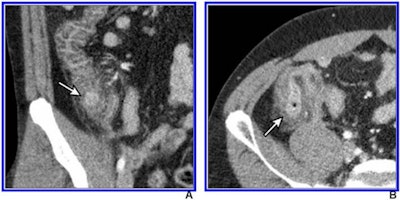

Intravenous contrast-enhanced 2-mSv 4-mm-thick transverse and coronal (B) CT images show inflamed diverticula (arrows), segmental colonic wall thickening, and adjacent pericolic fat stranding. Images courtesy of the American Roentgen Ray Society and the American Journal of Roentgenology.

Intravenous contrast-enhanced 2-mSv 4-mm-thick transverse and coronal (B) CT images show inflamed diverticula (arrows), segmental colonic wall thickening, and adjacent pericolic fat stranding. Images courtesy of the American Roentgen Ray Society and the American Journal of Roentgenology.The researchers found that true positives, true negatives, sensitivity, and specificity results between the two groups were not statistically significant, demonstrating the efficacy of low-dose CT for this indication, they concluded.